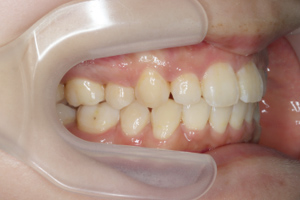

症例

矯正歯科専門の歯科医師が専門的な知識と確かな実績を

もとに患者様にあった最適な治療プランをご提案します。